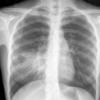

Case 2 Lingular pneum PA

Date: 04/17/2005

Views: 5955